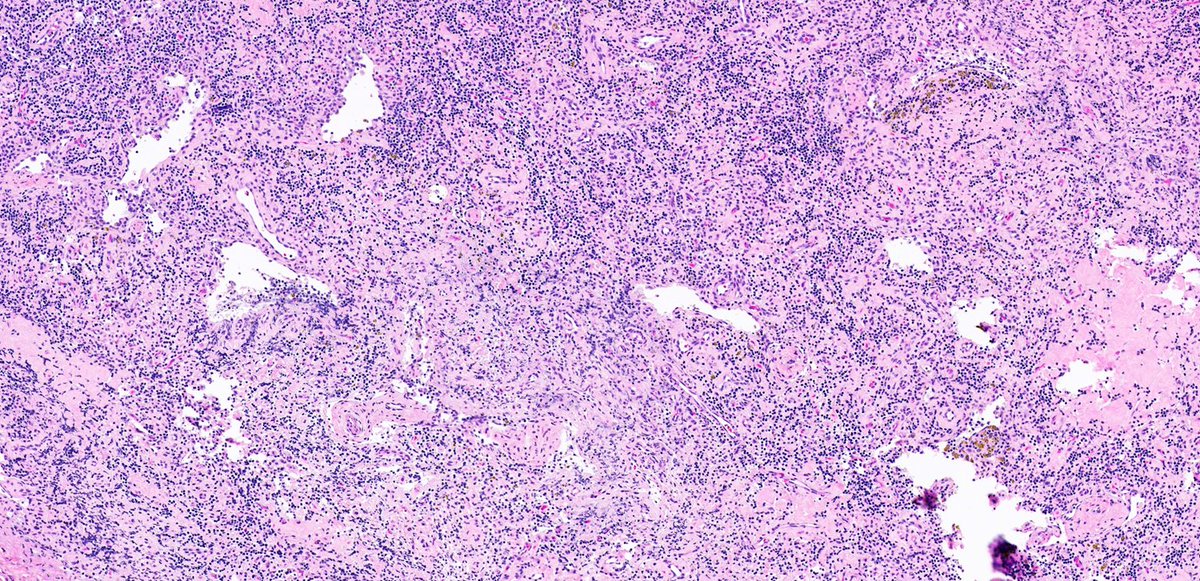

Vascular transformation of sinuses, also called nodal angiomatosis: Usually found incidentally after resection of a nearby tumor, due to obstruction of lymphatic efferent vessels or venous obstruction #Hemepath #PathX #Surgpath #PathTwitter #MedEd

Composed of a complex network of anastomosing blood vessels of variable sizes with fibrosis, irregularly branching vascular slits with extravasated red blood cells and interstitial hemosiderin deposition #Hemepath #PathX #Surgpath #PathTwitter #MedEd